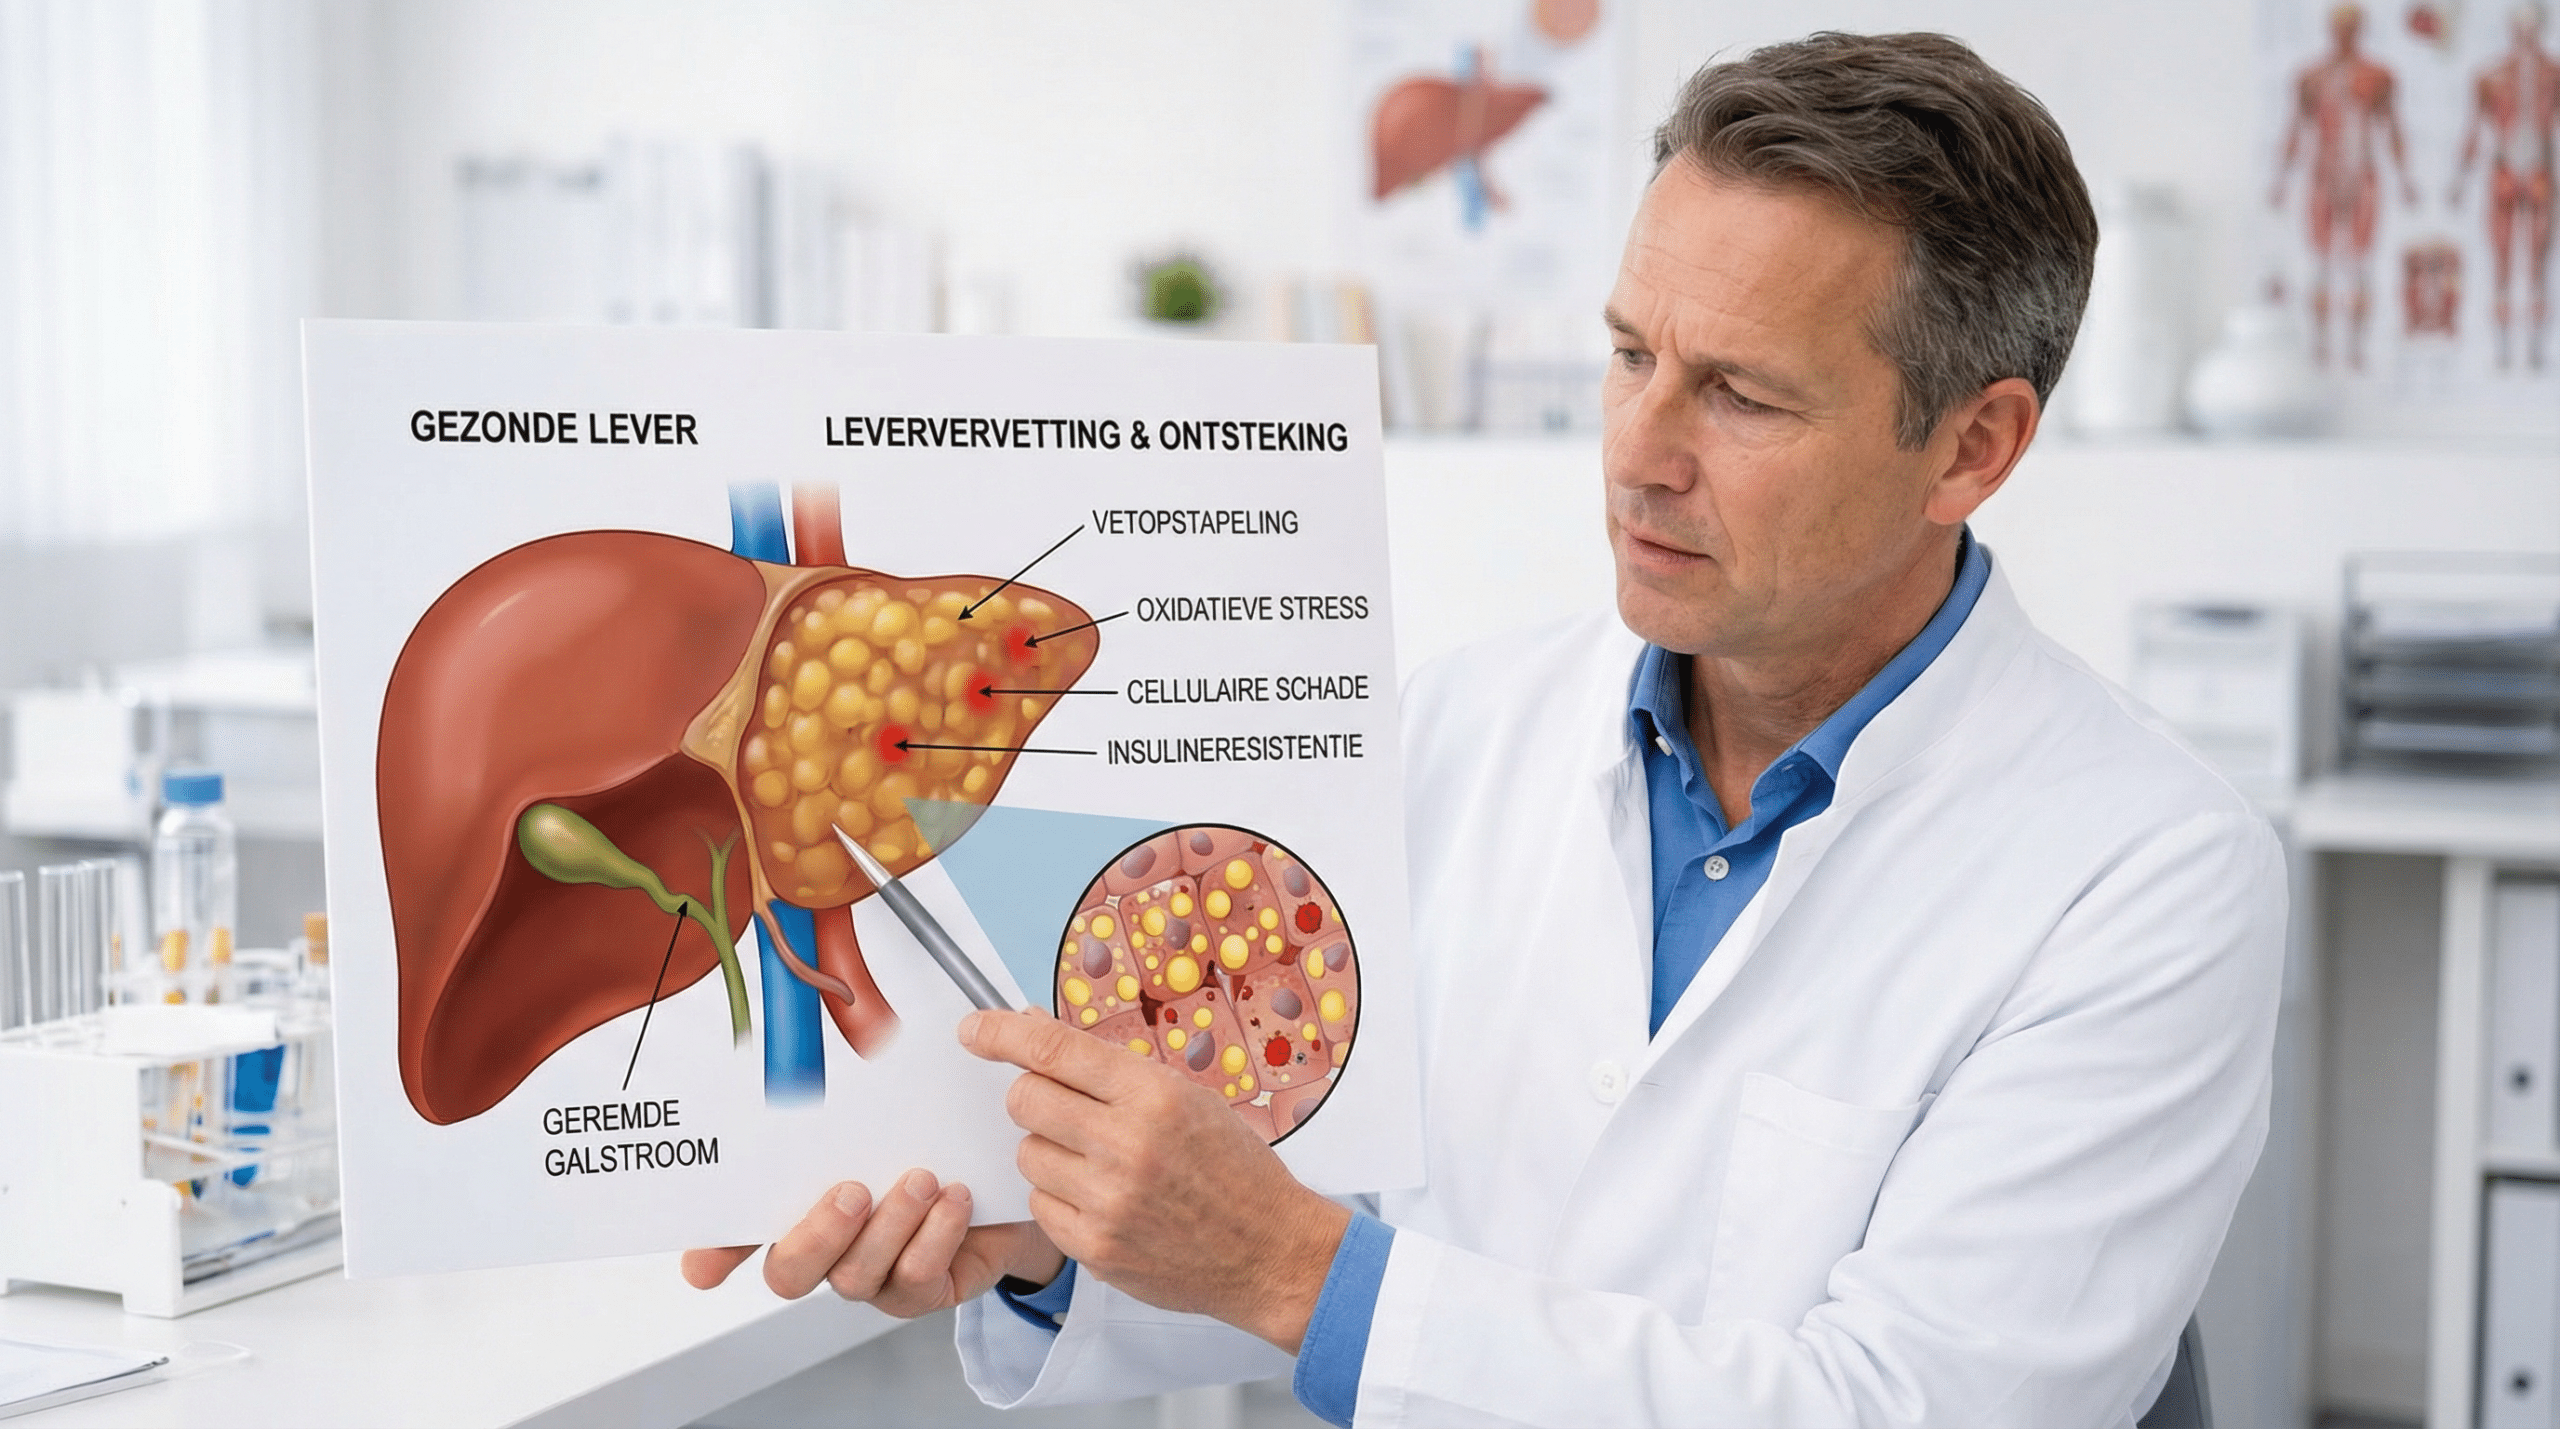

Om het verschil te begrijpen, moeten we eerst begrijpen hoe de lever vet verwerkt en wat er misgaat bij leververvetting.

Een gezonde lever met een goed functionerend metabolisme verwerkt vetten soepel en houdt de leverenzymen binnen normale waarden.

Door vetopstapeling raken levercellen beschadigd — de kleine vetdruppeltjes in de cellen verstoren de normale leverfunctie, veroorzaken oxidatieve stress en activeren ontstekingsreacties die de schade verder uitbreiden.

Vanaf je 40e neemt de gevoeligheid van je cellen voor insuline geleidelijk af — insulineresistentie zorgt ervoor dat de lever meer vet aanmaakt en minder efficiënt afbreekt.

Chronische laaggradige ontsteking — mede veroorzaakt door buikvet, bewerkte voeding en stress — versnelt dit proces dramatisch.

Vanaf je 40e neemt de insulinegevoeligheid van je cellen geleidelijk af — de lever reageert hierop door meer vet aan te maken en minder efficiënt af te breken, wat vetopstapeling versnelt.

Tegelijkertijd activeert chronische laaggradige ontsteking — gevoed door buikvet, bewerkte voeding en chronische stress — ontstekingspaden in het leverweefsel die de cellulaire schade versnellen.